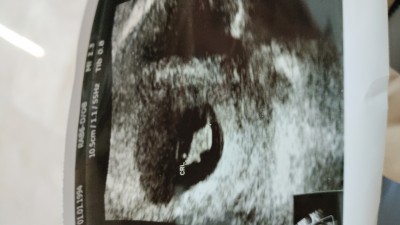

Kızlar nedense tamamen hissiyat olarak ikiz gibi ama doktorum öyle bişi söylemedi size danışmak istedim gerçi sağlıklı olsun da

Ikiz gibi durmuyor canım yinede ikizse ileriki haftalarda belli.olur rabbim gönlüne göre versin insallah